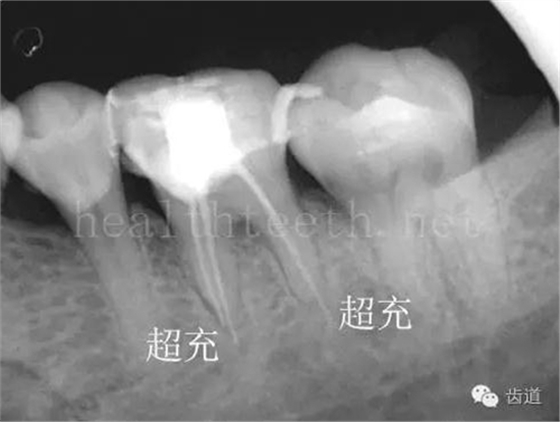

因?yàn)楸旧聿桓阏衬げ。占降牟±邢?,大多是同事收?/span> 頰粘膜扁平苔蘚 舌粘膜扁平苔蘚 舌緣創(chuàng)傷性潰瘍 長期戴活動義齒不當(dāng)或是戴不良修復(fù)義齒造成的口腔粘膜潰瘍,應(yīng)該引起高度警惕,因?yàn)檫@種潰瘍?nèi)菀装┳?/span> 黑毛舌 舌息肉,該患者同時伴有胃、食管息肉,后來看內(nèi)科了,具體情況不詳 四、孩子的牙齒問題 乳牙未退,牙根穿出牙齦對上唇粘膜造成刺激 乳牙滯留,也是孩子在退牙過程中最容易遇到的問題 五、牙齒發(fā)育上的問題 變色牙 氟斑牙 釉質(zhì)發(fā)育不全 四環(huán)素牙 牙神經(jīng)治療后的牙齒變色 10歲孩子剛剛萌出的牙齒變色 2、埋伏牙 左上乳3滯留,恒3未見萌出,曲面斷層片顯示牙齒埋伏 通過CT片確定埋伏牙齒具體的位置,顯示距離左側(cè)上頜竇很近,偏唇側(cè),這為手術(shù)定位提供了方便 手術(shù)中切斷、完整拔出,未損傷上頜竇 其他埋伏牙 3、多生牙 病例1 病例2 病例3,同時多生兩顆牙齒 4、各種畸形牙 畸形過小牙 融合牙:恒牙和乳牙都可以發(fā)生融合的情況(兩顆牙齒長在了一起) 畸形中央尖:在牙齒的中央,兩個牙尖之間又多長出一個牙尖,由于進(jìn)食的磨耗很容易造成磨穿,神經(jīng)就會與外界相通,出現(xiàn)牙髓炎的癥狀 六、牙齒的外傷 牙冠折斷 牙根折斷 烤瓷牙打樁修復(fù)后牙根折斷 外傷后牙齒的全脫位,應(yīng)該保留牙齒盡早做再植手術(shù) 七、牙齒的慢性損傷 牙頸部楔狀缺損 牙冠劈裂及完整拔除后的情況 牙根縱裂及拔除后的情況 牙隱裂,牙齒表面有肉眼看不到的裂紋,細(xì)菌通過其進(jìn)入牙髓,容易出現(xiàn)牙髓炎癥狀,嚴(yán)重可以造成牙齒的劈裂 這是一位來中國學(xué)習(xí)的俄羅斯大學(xué)生的牙齒,已經(jīng)做過了根管治療,牙齒咬合面有隱裂,通過鋼絲結(jié)扎固定,做鑄造金屬冠修復(fù)。 八、牙髓炎、根尖周炎 下面圖片都是慢性根尖周炎的病例,有了齲齒,進(jìn)一步發(fā)展就是牙髓炎,如果此時沒有得到及時的治療,疾病會逐漸發(fā)展破壞到根尖的骨質(zhì),將骨質(zhì)破壞后就在牙齦上出現(xiàn)一個膿瘺,此時患者不再感覺到牙齒的疼痛了,往往忽視了治療,但是這種不痛并不是疾病好轉(zhuǎn)了,而是因?yàn)榧膊〉难仔詽B出得到了引流,這個膿瘺會出現(xiàn)有時候變大了,有時候又變小了,但是如果不治療是不會自己愈合的,只有經(jīng)過完善的根管治療后才有好轉(zhuǎn)的可能,但是在疾病的治療中時間是起決定作用的,時間拖得越晚,好轉(zhuǎn)的可能性越小,經(jīng)過根管治療后如果膿瘺還是沒有消失,就需要做根尖刮治術(shù),如果仍然沒有好轉(zhuǎn),就只能做根尖切除術(shù)了,這對牙齒的穩(wěn)固是不利的。下面圖片中在膿瘺中插入了一個牙膠尖,是我們做根管充填用的材料,是非常軟的,就是在口腔牙齦瘺管的地方插進(jìn)去,通過拍牙片可以清晰地看到它到達(dá)的位置,從而確定發(fā)病的牙齒,此處是為了讓大家看得更清楚。 門牙兩個膿瘺 烤瓷牙修復(fù)后牙齦出現(xiàn)兩個膿瘺,插入牙膠尖,牙片顯示牙膠尖到達(dá)的位置就是根尖炎癥的位置,根尖骨質(zhì)密度降低(發(fā)黑的地方) 牙齒根尖膿瘺,治療前、中、后的圖片對照,完善根管治療后膿瘺明顯消失了 牙髓炎和根尖炎治療的關(guān)鍵就是根管治療 合格的根管充填治療 不良的根管充填治療 九、關(guān)于智齒(第八顆牙) 四顆長不出來的智齒 智齒反復(fù)發(fā)炎造成的頰瘺,膿腫切開引流后面部會留疤 智齒造成的頜骨囊腫,手術(shù)切除后需要植骨 十、各種錯合畸形 開合 深覆合 深覆蓋,上頜前突 反合(地包天) 牙齒排列擁擠 來源:牙醫(yī)愛看的 KQ88口腔醫(yī)學(xué)網(wǎng)